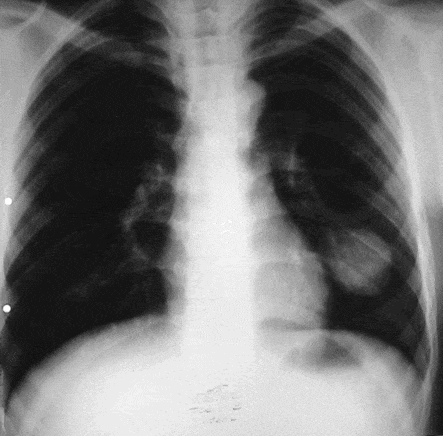

Для подтверждения наличия паразитов в легких требуется тщательная диагностика, которая включает как клинические, так и аппаратные исследования организма:

- серологический анализ и общий анализ крови;

- рентгенография;

- микроскопия выделяемой мокроты;

- компьютерная томография (КТ) органов.

Аппаратные исследования проводятся с целью определения:

- местоположения кист;

- степени поражения (размер кист, стадии их развития);

- возможных осложнений.

Подтверждение диагноза осуществляется на основе серологического анализа, который выявляет реакцию антител к клеткам паразита. Общий анализ крови может показать отклонения в скорости оседания эритроцитов (СОЭ). Исследование мокроты также может подтвердить наличие гельминтов, если киста прорвалась, так как в выделениях могут находиться фрагменты личинок. В некоторых случаях может потребоваться проведение дополнительных обследований, таких как бронхоскопия.